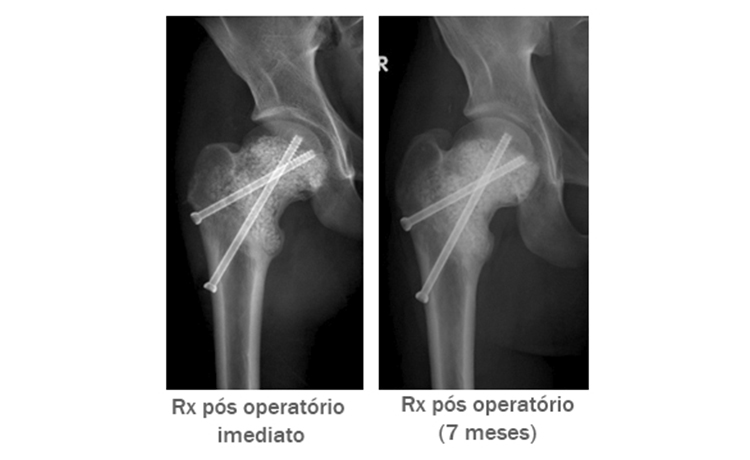

Paciente: Homem, 16 anos, com um grande cisto ósseo aneurismático na proximal do fêmur.

Operação: Na primeira operação a cavidade foi preenchida com osso do próprio paciente, e na segunda operação com substituto ósseo à base de CaP. Em ambos os casos os enxertos foram absorvidos. Na 3ª operação foram utilizados 60 cc/2.0-3.15 mm de BonAlive® granules.

Evolução Clínica: A cicatrização pode ser observada devido às características de osteoestimulação* e lenta reabsorção do BonAlive® granules.